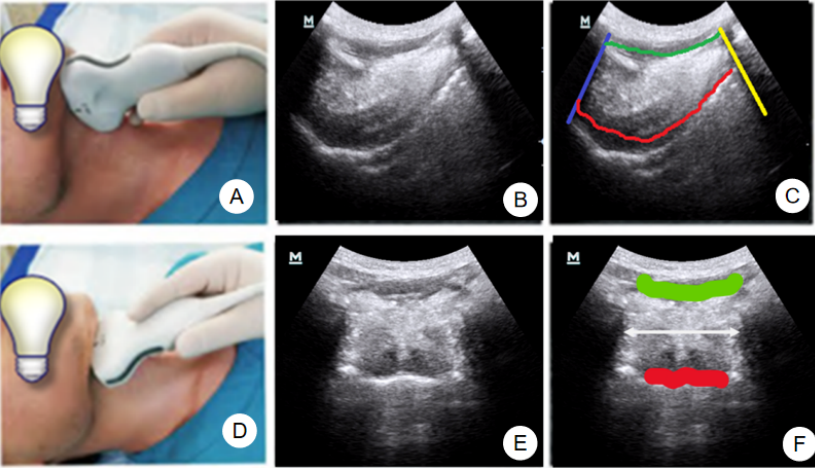

1. 舌骨平面的扫查

在扫查中,我们将低频凸阵超声探头置于下颌处纵切面扫描,可以看见舌体、舌前间隙、还有下颌舌骨肌。图4中A为凸阵探头置于下颌区纵切的示意图,B为该示意图下的超声影像,C中蓝色为颌骨阻挡后形成的无回声区域,黄色为舌骨阻挡后形成的无回声区域,红色为舌体背面,白色虚线为舌体的宽度。由于男性甲状软骨的存在,此手法会有一定的难度,可以采用横切手法做扫查,图4中D为凸阵探头置于下颌区横切的示意图,E为该手法下的超声影像,F中绿色为舌底肌群,红色为舌背面,白色双箭头线为舌根的宽度。

图片图4  舌骨平面扫查